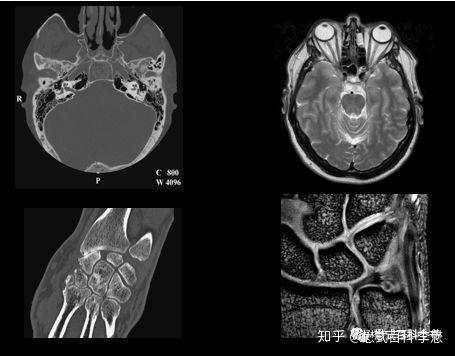

3 0t和1 5t磁共振扫描序列有哪些不同 知乎

1 5t与3t核磁共振 Mri 知乎

临床医生应该知道的磁共振知识 如何判断磁共振图像 知乎